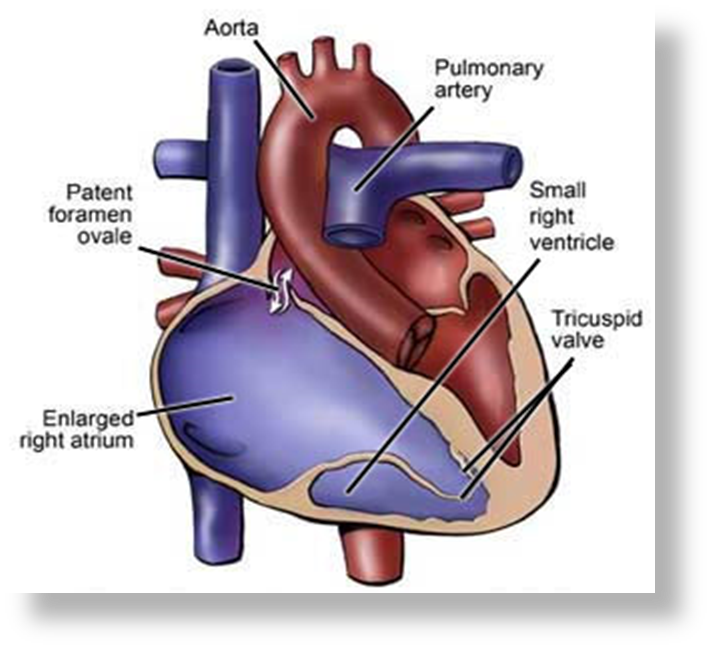

What is Tricuspid Atresia?

is a condition present at birth (congenital heart disease), a solid wall of tissue blocks the blood flow between your right heart chambers.

Ebstein's anomaly

is a condition in which a malformed tricuspid valve sits lower than normal in the right ventricle, causing blood to flow back into the right atrium (TR).

Atrisia is?

Absent

What is ebstein?

displacement of the tricuspid valve leaflets downward into the right ventricle, leading to a functional stenosis.